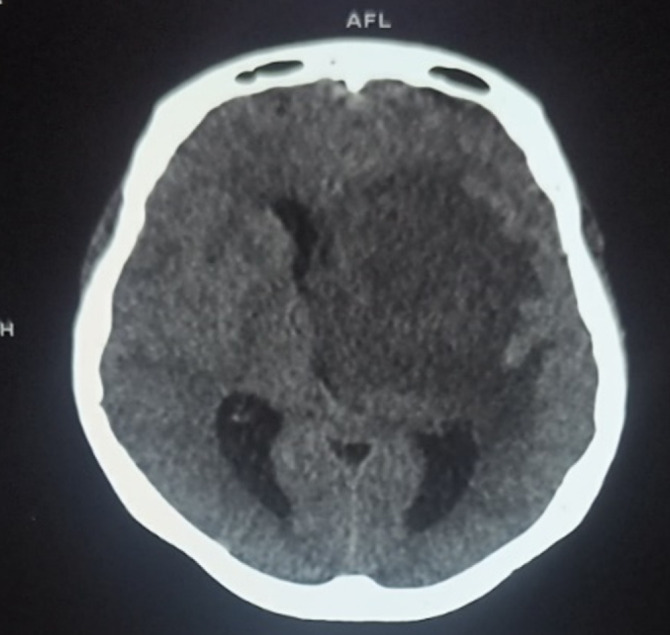

Extended-spectrum beta-lactamase-secreting Enterobacteriaceae (ESBL-E) infections constitute a real global public health problem, particularly in sub-Saharan Africa. We report here two cases of ESBL-E meningoencephalitis in young female patients occurring in a gestational context observed at the infectious and tropical diseases department of the Point G university hospital in Bamako. The first woman, who recently had an abortion, was being treated with ceftriaxone when she was admitted for meningeal syndrome and pyramidal syndrome associated with brain damage. Escherichia coli resistant to penicillins and cephalosporins was isolated from cerebrospinal fluid (CSF), blood and a purulent genital swab. She recovered under meropenem treatment for 21 days, with few sequelae.The second had given birth in the weeks prior to the onset of generalized infection. She was admitted for meningeal syndrome and pyramidal syndrome associated with several cerebral lesions disclosed by the CT scan. Multidrug-resistant E. coli was isolated from CSF and genital purulent sample. She recovered (with sequelae) under treatment with meropenem for 21 days. These two observations show that female genital infections (postpartum or post abortum) with E. coli can cause forms as serious as meningoencephalitis, in addition to the abortion they cause. ESBL-E -producing strains may be involved and represent a major therapeutic challenge. Better infection prevention and control would prevent multi-drug-resistant infections and their spread. Regulating the use of carbapenems and other antibiotics still effective against multi-resistant bacterial strains within the framework of global health (one health) would avert an incurable pandemic of highly resistant and emerging bacteria (HRB).